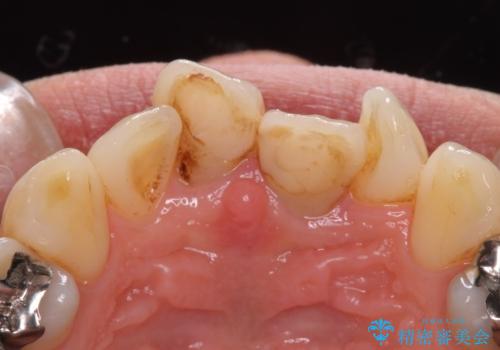

- 前歯の変色とガタつきがきになるとのことで来院されました。

元々根管治療がされていたにも関わらず被せ物が作られておらず、このままではどんどん変色が進んでいってしまう状態でした。

歯をある程度削ることにはなりますが、被せ物にすることで歯の変色を隠し短期間でキレイな口元に仕上げることができました。